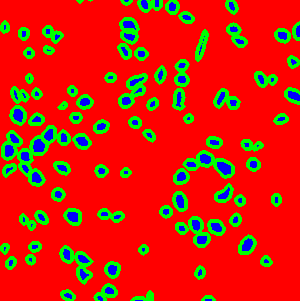

The task of nuclei segmentation can be roughly divided into two stages: the first stage is extracting the foreground(nuclei), the second stage is segmenting the connected foreground area into separated nuclei and finding out the boundary of each nucleus. Our method intends to merge these two steps by extracting the nuclei and their edges at the same time. That is the reason why it is named ”nuclei-boundary(NB) model”. As shown in Fig.3, the output of the NB model has three channels, each has the same height and width with the input image. Its values represent the probabilities of each pixel being , or class, respectively. The manual annotation for our segmentation problem is the boundary of each nucleus. A pixel belonging to the class means that it is on or inside an annotated boundary and within 2 pixel from the boundary. Pixels of the class are those that are inside annotated boundary but are not pixels. Correspondingly, the output can be regarded as an RGB image and the estimated maps of the , and are represented by red, green and blue, respectively, as shown in Fig.3. To generate the ternary mask for training, we apply a morphology operator to each nucleus to obtain the pixels, and then subtract pixels from the nucleus to get pixels.

Figure 6 shows how our method segments the nuclei step by step. The color variety is well controlled by the color normalization procedure. The prediction result shows clear nuclear areas and nucleus boundaries. In the final segmentation result and ground truth image, each nucleus is represented by a different color.